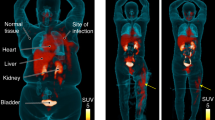

Here, we describe an extension of our silicon fluoride acceptor (SiFA) protocol for 18F-labeling of peptides that addresses challenges associated with preparing a clinical-grade (Tyr3)-octreotate (TATE) tracer for diagnosis of neuroendocrine tumors (NETs). After several iterations of protocol optimization (e.g., finding the optimal pH at which the isotopic exchange (IE) reaction produces high radiochemical yields (RCYs)), the SiFA technology achieved clinical applicability, as showcased by radiosynthesis of [18F]SiFAlin-TATE ([18F]SiTATE), the first SiFA peptide used in the clinical diagnosis of NETs. The TATE peptide binds to somatostatin receptors associated with NETs. Radiolabeled TATE derivatives are routinely applied in clinical oncological PET imaging. The (SiFA) 18F-labeling technology is based on the IE of a 19F atom for a radioactive 18F atom, a highly efficient labeling reaction under mild conditions. The 19F is part of a biomolecule bearing the SiFA building block, composed of a central silicon (Si) atom, a 19F atom connected to the Si atom, and two Si-bound tert-butyl groups. The IE proceeds through a penta-coordinate bipyramidal intermediate, followed by elimination of non-radioactive 19F, yielding the labeled compound in high RCYs at room temperature (22 °C). The simplicity and lack of side-product formation of this approach enable a one-step, kit-like preparation of structurally complex and unprotected radiopharmaceuticals. Compounds such as peptides used for tumor imaging in nuclear medicine can be 18F-labeled without the need for complex purification protocols. [18F]SiTATE can be synthesized within 30 min in preparative RCYs of 42%, radiochemical purity of >97% and high molar activity of 60 GBq/µmol.

Ilhan, H. et al. Biodistribution and first clinical results of 18F-SiFAlin-TATE PET—a novel 18F-labeled somatostatin analog for imaging of neuroendocrine tumors. Eur. J. Nucl. Med. Mol. Imaging 47, 870–880 (2019).

Ilhan, H. et al. First-in-human 18F-SiFAlin-TATE PET/CT for NET imaging and theranostics. Eur. J. Nucl. Med. Mol. Imaging 46, 2400–2401 (2019).

Niedermoser, S. et al. In vivo evaluation of 18F-SiFAlin–modified TATE: a potential challenge for 68Ga-DOTATATE, the clinical gold standard for somatostatin receptor imaging with PET. J. Nucl. Med. 56, 1100–1105 (2015).